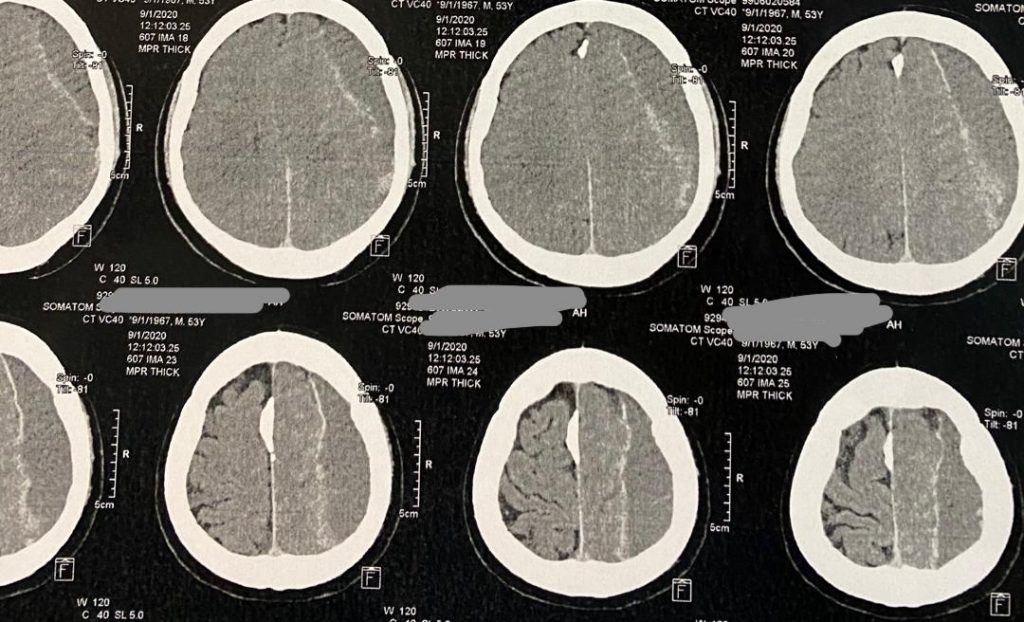

تصاویر قبل از عمل

بیمار آقای میانسال با سردرد و ضعف نیمه سمت راست بدن مراجعه کرده بودند. با تشخیص هماتوم ساب دورال مزمن توسط دکتر فهیم باغبان مورد جراحی قرار گرفتند.